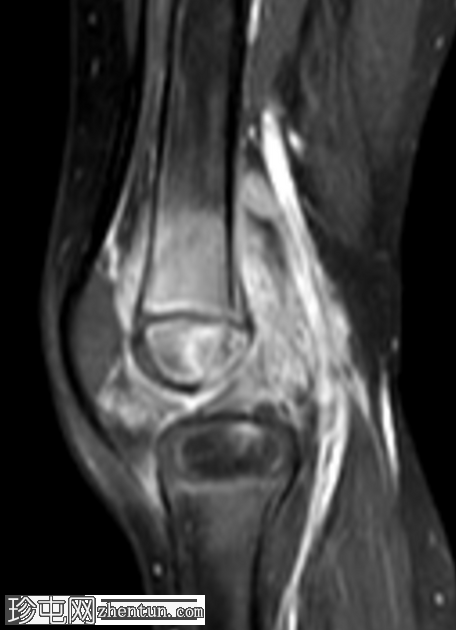

矢状位

T2加权像

右膝专用MRI显示股骨外侧髁后方髓内有一边界清晰的病灶,大小为1.6 x 0.9 cm,中心T1呈低信号,T2/STIR呈高信号,周围可见薄层T1高信号环(半影征)。

增强扫描显示病灶环强化,周围骨髓强化,骨骺和干骺端亦强化。

周围骨髓水肿广泛,在STIR序列上呈高信号,在T1加权像上呈低信号。

邻近软组织轻度水肿,未见脓肿形成或明显窦道。

影像学表现为股骨外侧髁后方亚急性骨髓炎(布罗迪脓肿),伴周围骨髓水肿和轻度邻近软组织水肿。